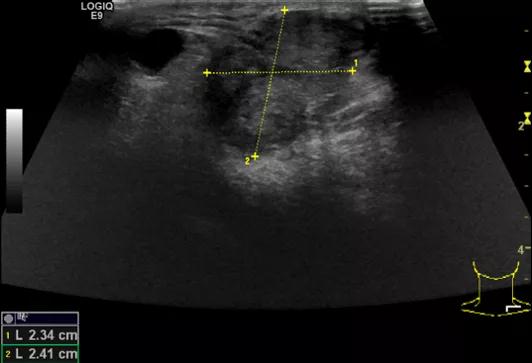

随后,徐栋教授进一步分享了五个临床实战病例,带来了更直观的热消融治疗经验。第一个病例是62岁肺癌患者,术后1年余发现双侧锁骨上淋巴结复发,侵犯神经,存在静脉回流、淋巴回流障碍,肿胀、疼痛非常明显。影像显示患者淋巴结边界不清、形态不规则,存在浸润,血流强化增强。由于患者在系统治疗后进展,且主要目的缓解症状、减瘤。局麻下行热消融术,从后向前逐层消融,热消融之后超声造影即刻评估显示完全充盈缺损,完全覆盖病灶。

(病例1图例)